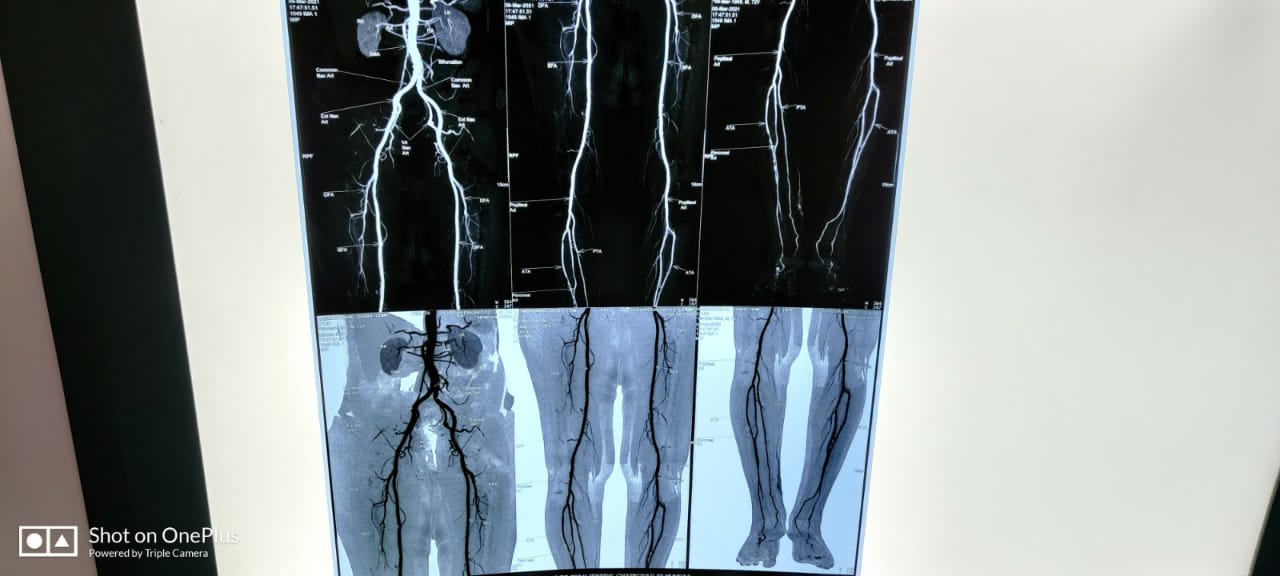

Patient’s Successfully Treated with Diabetic Foot Problems